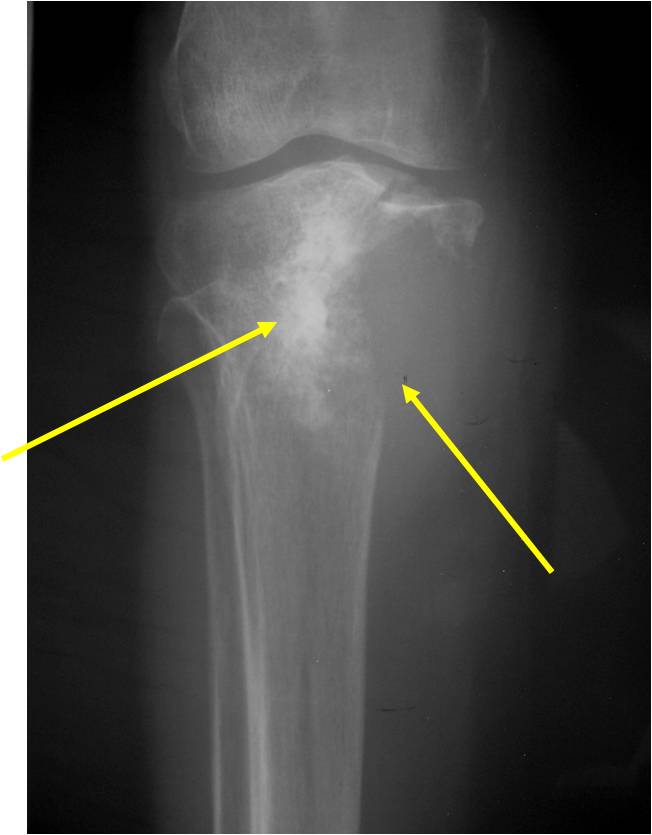

Radiographic Presentation

Radiology emulates pathology: Biphasic Tumor

- One region low grade chondrosarcoma

- Second more aggressive area with bone destruction, lysis of calcification, soft tissue mass

- Cortical permeation and a soft tissue mass in 70% of cases

Ill-defined, lytic intraosseous lesion

- Or extraosseous soft tissue mass

- Devoid of calcifications in continuity with lesions having the features of a cartilaginous tumor

Characteristically abrupt transition between chondroid tumor and dedifferentiated, lytic component

Bone may be expanded and adjacent cortex thickened

(Right Arrow)Aggressive Lytic Area (Dedifferentiated Sarcomatous Component) Cortical Destruction Soft Tissue Mass without Calcification